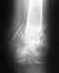

Доброго времени суток. 30 марта 2011 года, подвернул правую ногу, почувствовав в последствии сильную боль и смещение кости. поехал сразу в травматологию-положили в больницу. Выписали на амбулаторное лечение 5 апреля 2011. Сейчас хожу дома на костылях без нагрузки в гипсе, наложенном на лангетку.Хотел бы узнать как скоро можно будет вернуться к полной нагрузке на ногу.снимки прилагаются.

• Кликните для загрузки файла IMG00030.jpg

Хотелось бы увидеть боковую проекцию, но обычно притаких повреждениях гипсовая иммобилизация накладывается на 2,5 месяца, затем ЛФК, физиолечение с восстановлением функции в голеностопном суставе и постепенное увеличение нагрузки. Работоспособность, в зависимости от специальность, восстанавливается от 4 до 6 месяцев. В нашем отделении, при отсутствии противопоказаний, выполняется оперативное вмешательство